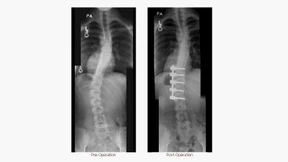

Sie selbst ist überrascht von ihrem großen Erfolg: Die amerikanische Golfspielerin Stacy Lewis leidet an Skoliose, hat Schrauben im Rücken und führt die Golf-Weltrangliste an.